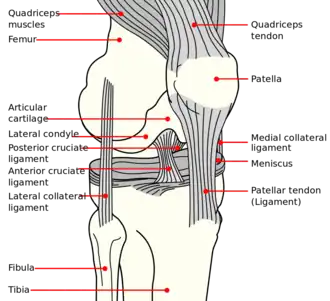

Bones of the right leg. Anterior surface.

Bones of the right leg. Anterior surface. -

Right knee in extension. Deep dissection. Posterior view.

Right knee in extension. Deep dissection. Posterior view.